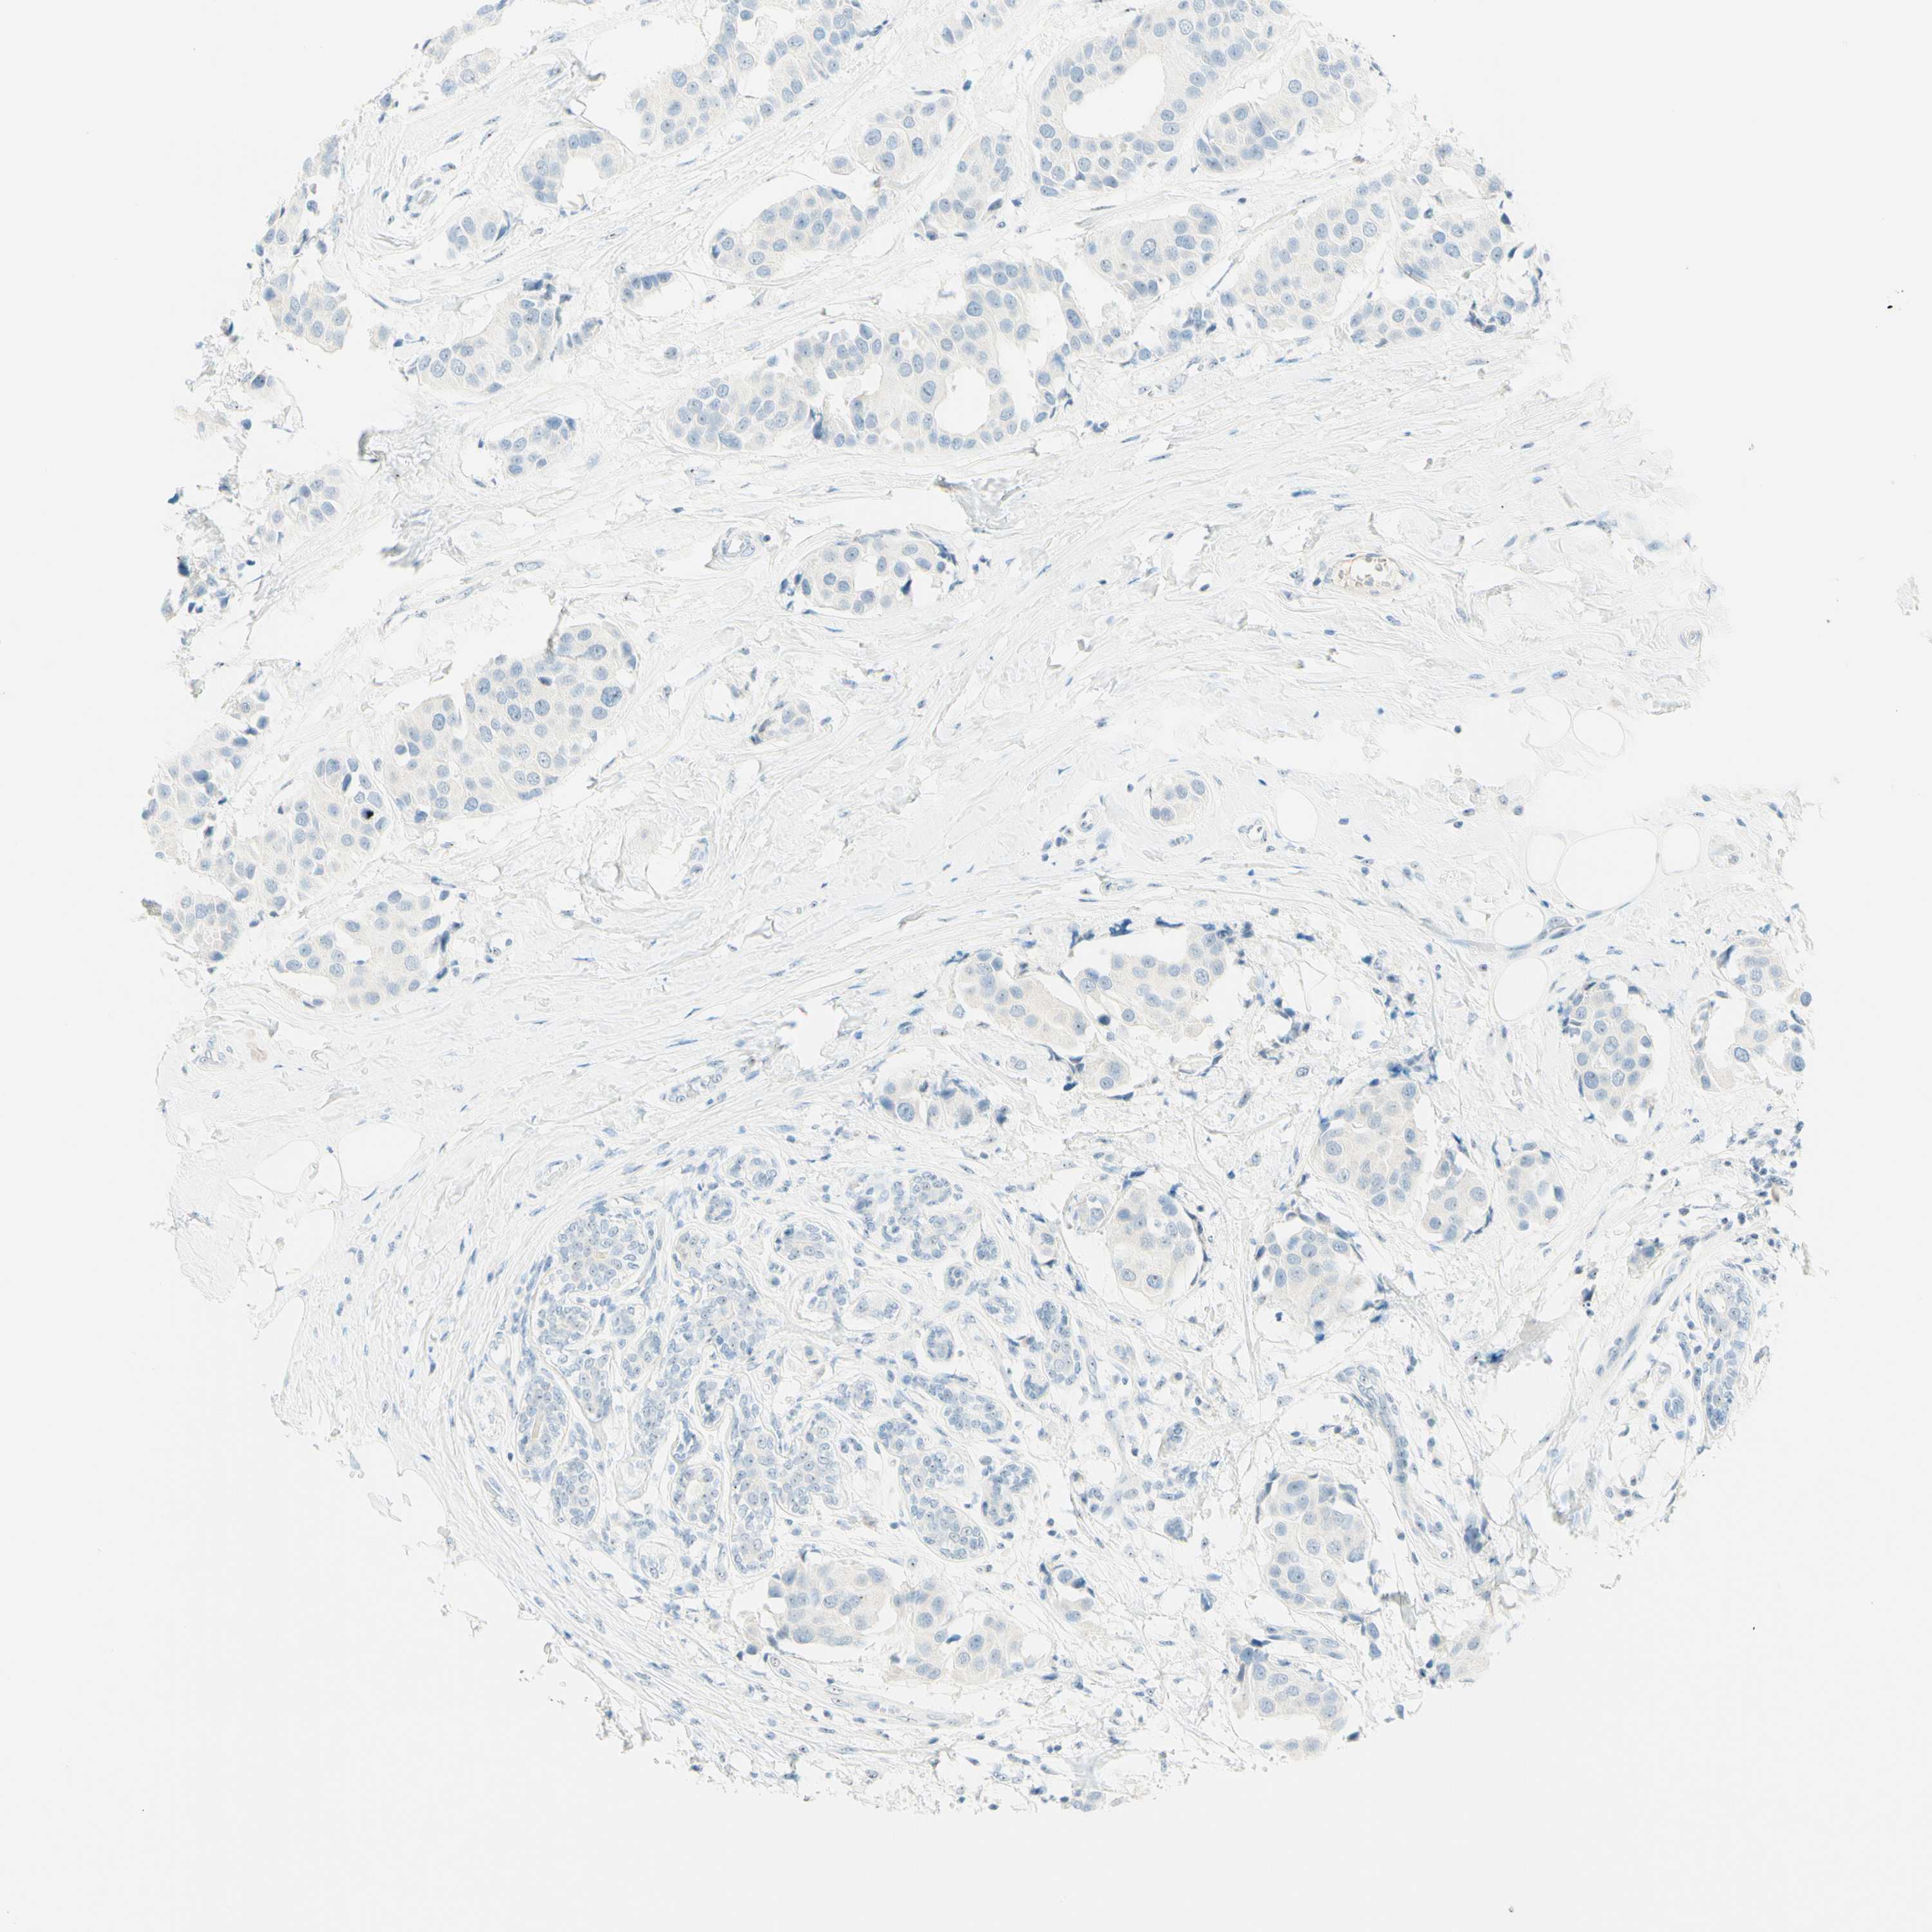

CANCER BREAST CANCER Show tissue menu

BRCA TCGA BRCA VALIDATION PROTEIN EXPRESSION

Breast cancer

Human cancer

Breast invasive carcinoma